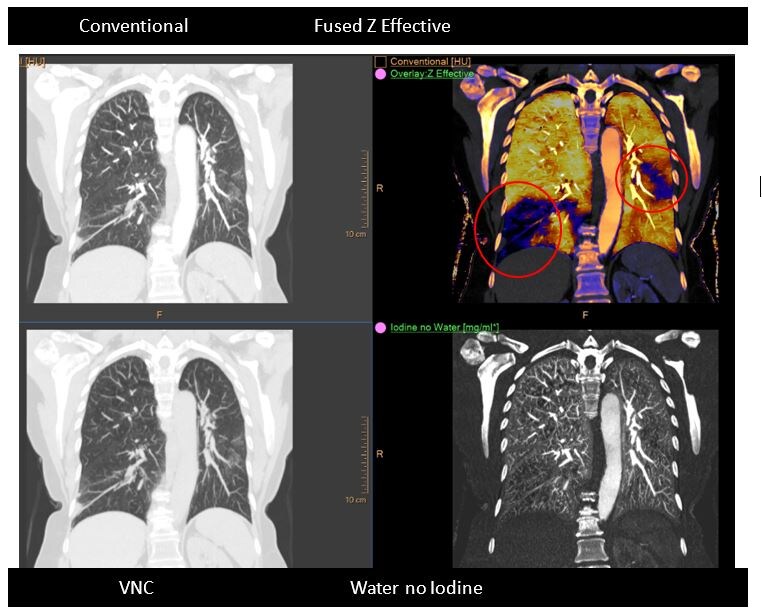

Small pulmonary emboli (PE) can be difficult to identify on conventional CT images alone, and perfusion defects in the area of the PE can be overlooked.

The IQon Spectral CT aids the radiologist by providing spectral results that can help identify perfusion defects. Multiple spectral results available with every patient scanned on the IQon Spectral CT can aid the radiologist in the ability to identify multiple perfusion results.

In this example, the patient presented with a suspected PE. After reviewing the conventional scan, spectral results were applied, resulting in multiple perfusion defects being identified by the radiologist in both lungs.

Images courtesy University Hospitals, Cleveland, Ohio, USA